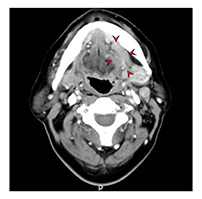

전산화단층촬영법(Computed Tomography, CT)

악골 및 연조직의 진단에 사용합니다. 악성 여부에 대한 영상학적 진단, 침범 범위 및 전이여부 등을 알아보기 위한 검사입니다. 임상적 병기 진단에 자기공명영상(MRI)와 더불어 주로 사용되며 수술 가능여부 및 수술 범위 결정 등에 기본적으로 필요한 검사입니다. 초음파 검사와 함께 생검시 종양으로의 정확한 접근을 위하여 사용되기도 합니다. 혈관과 림프선의 구분, 종양의 경계부 확인 등을 위하여 조영제를 사용합니다

좌측 설암 전산화단층촬영 이미지

[좌측 설암 전산화단층촬영 이미지]